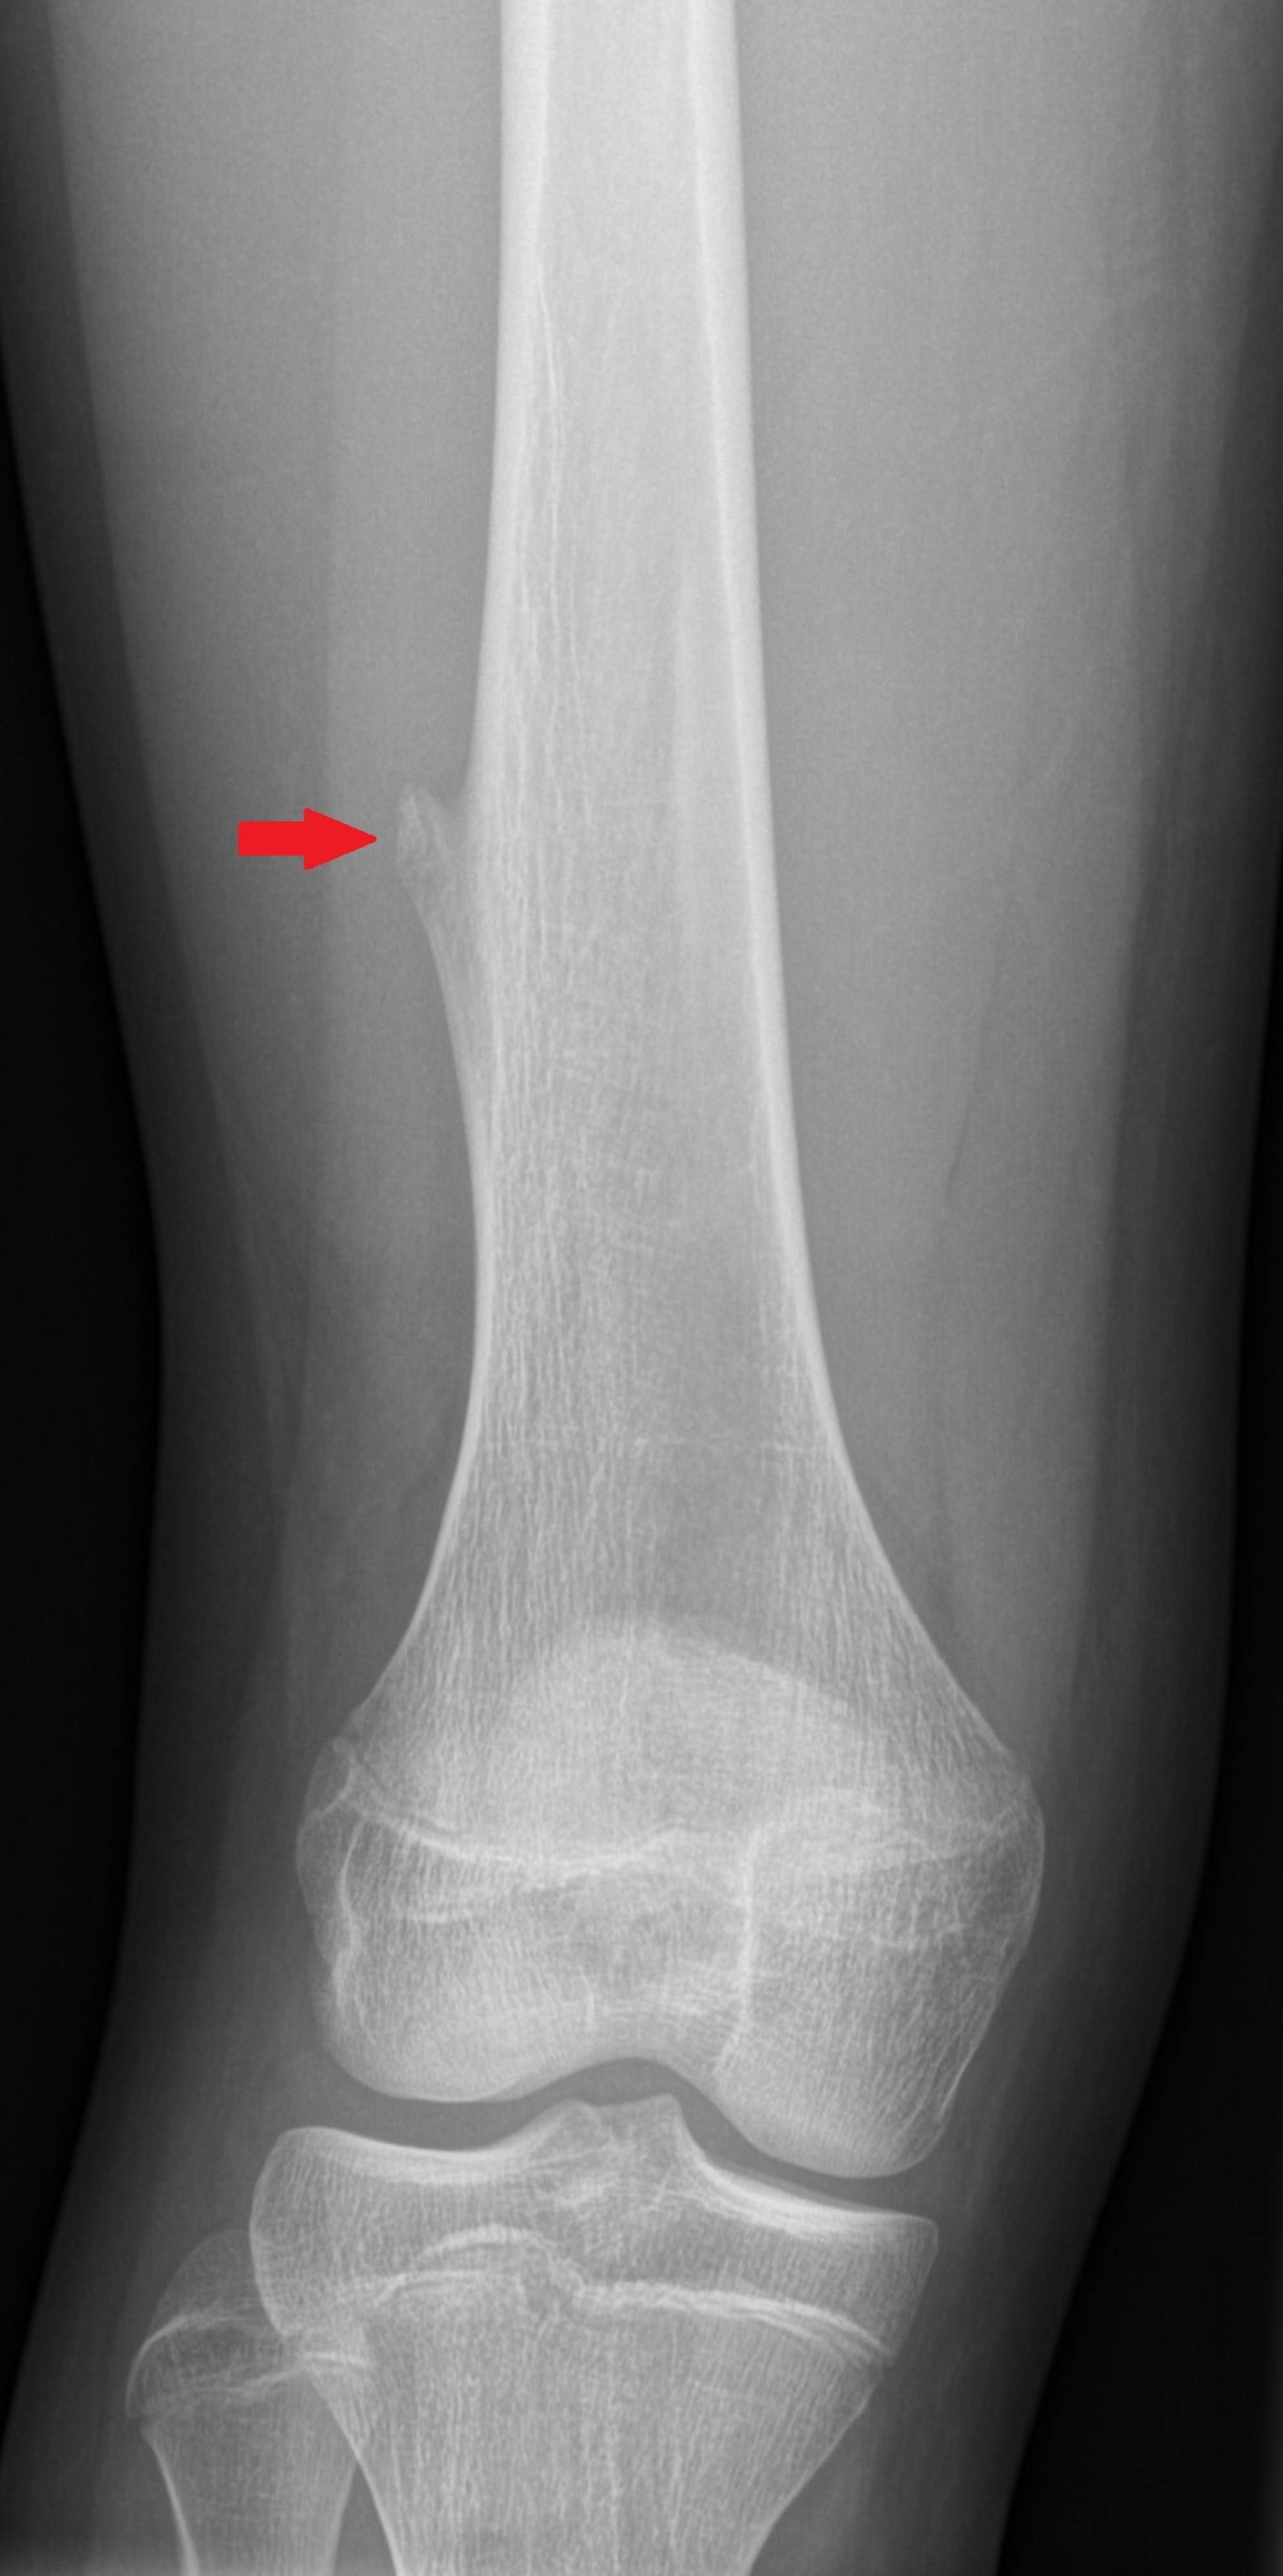

Tavoitteena on selvittää luukasvaimen laatu ja mahdollinen levinneisyys. Lasten ortopedin suorittama tutkimus on lähtökohtana jatkotutkimustarpeiden määrittelemiseksi. Luukasvainten diagnostiikassa röntgenkuvantaminen on ensisijainen menetelmä. Lisäksi tapauskohtaisesti lääkärin harkinnan mukaan luuta sekä kasvaimen levinneisyyttä voidaan kuvantaa myös muillakin kuvantamismenetelmillä kuten magneettitutkimus, tietokonetomografiatutkimus ja isotooppitutkimukset. Luussa esiintyvät muutokset pyritään selvittämään mahdollisimman tarkasti, jotta hoito voidaan kohdentaa oikein. Muutoksesta saatetaan ottaa kudosnäyte ja lapsesta tutkia verinäytteitä. Tutkimuslöydökset yhdessä muodostavat diagnoosin.